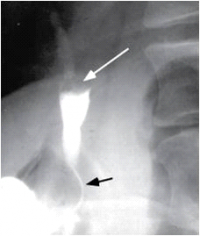

| תצלום 8.8: Percutanous trans-hepatic cholangiography (PTC) - תמונה שמאלית החץ מצביע על המחט והצנתר המוחדרים לדרכי המרה תמונה ימנית חץ מצביע על פגם בדרכי המרה G-כיס מרה 1- צינור מרה משותף. | |

- Percutaneus trans-hepatic cholangiography (PTC) (תצלום 8.8). בשיטה זו אפשר להדגים את דרכי המרה על-ידי ניקור מלעורי של הכבד. בניקור חודרים לכלי מרה בכבד ודרכו מזריקים חומר ניגוד לדרכי המרה ה"צובע" את העץ הביליארי. שיטה זו טובה בלוקים בערכי בילירובין גבוהים, שכן בהם אין לבצע את בדיקות הניגוד.

- בשיטה זו ניתן לבצע גם ניקוז קבוע של דרכי המרה על-ידי החדרת נקז לתוך דרכי המרה (PTD - percutaneus trans-hepatic drainage). התנאי להצלחת הבדיקה הוא דרכי מרה מורחבות, שאפשר לזהות בבדיקת אולטרה-סאונד של דרכי המרה (תמונה 9.8).

- בגישה זו אפשר גם לנקז את כיס המרה בחולים עם חסימות בצינור כיס המרה (איור 4.8) או לשלוף אבנים בעזרת מכשיר מיוחד ללכידת אבנים (Basket) (תצלום 10.8).